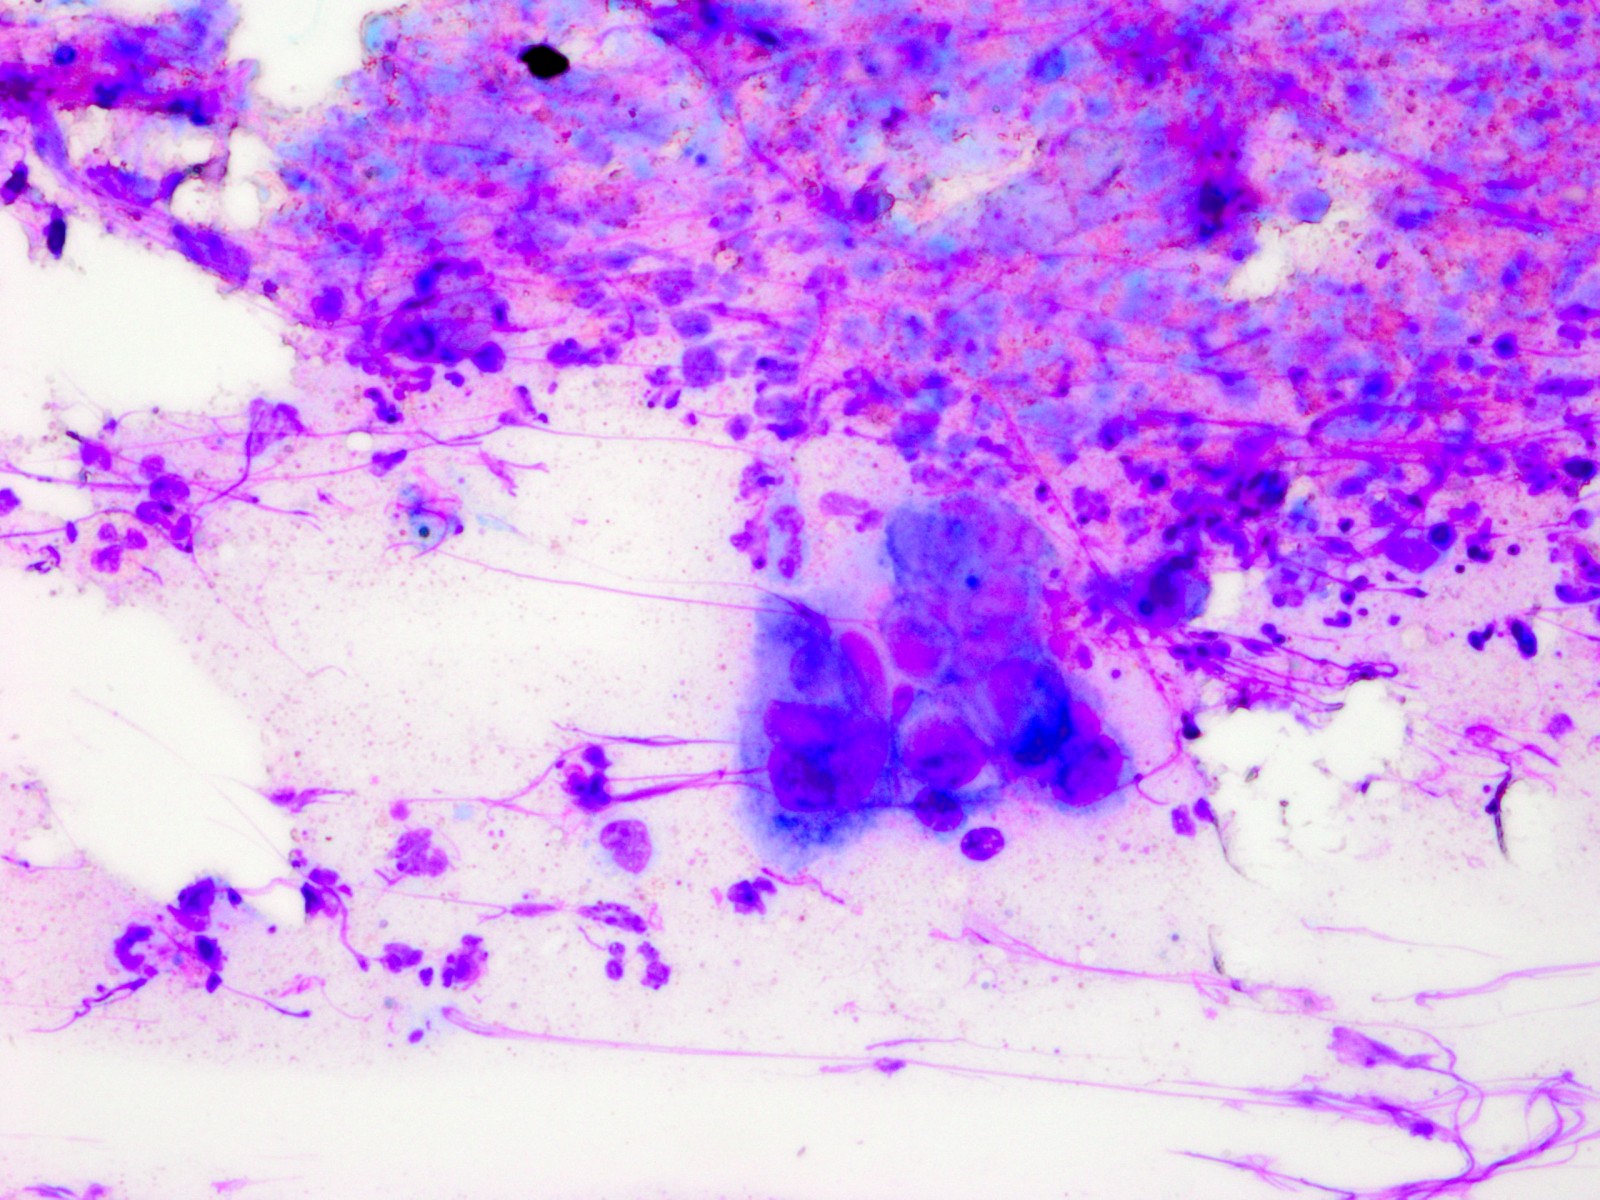

De Tzanck reuscellen hebben in het Diff-Quick preparaat een lichtblauw (basofiel)

cytoplasma en een homogene donkerblauwe of paarse kern (hyperchromatisch, sterk

aankleurend), en zijn zeer groot, veel groter dan een granulocyt. Het zijn geen

macrofagen of Langhanse reuscellen, het zijn conglomeraten van grote epitheliale

cellen (keratinocyten). Er kunnen in het preparaat ook losse van deze grote

hyperchromatische epitheelcellen liggen, maar diagnostisch is het vinden van

een klompje waarbij het cytoplasma samengesmolten is en de kernen tegen elkaar

aanliggen. Losliggende grote afgeronde epitheelcellen (Tzanck cells) kunnen

![Tzanck test met multinucleate giant cells (click on photo to enlarge) [source: www.huidziekten.nl] Tzanck test met multinucleate giant cells](../../../images/soa/Tzanck-test-4z.jpg) |

Tzanck

test |